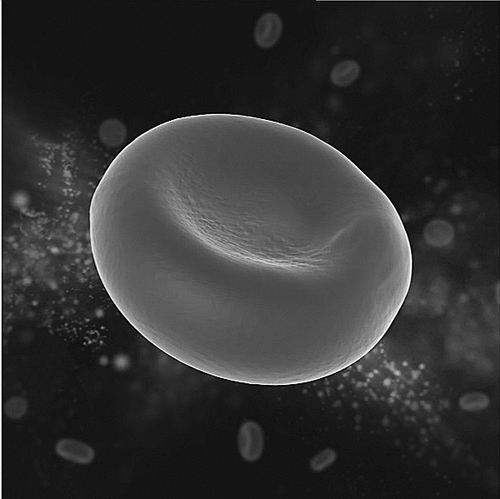

①人類(lèi)成熟紅細(xì)胞形態(tài)示意圖。

作為人體內(nèi)數(shù)量最多的細(xì)胞,紅細(xì)胞發(fā)揮著輸送氧氣和二氧化碳的功能,它穿行在大大小小的血管中,有時(shí)候還必須折疊自己以穿過(guò)那些狹小的毛細(xì)血管。這讓紅細(xì)胞“放棄”了自己的細(xì)胞核,在人體內(nèi)滿(mǎn)負(fù)荷工作大約120天。

紅細(xì)胞發(fā)育過(guò)程可以分為多個(gè)階段。成熟的紅細(xì)胞通常是雙凹圓盤(pán)形且沒(méi)有細(xì)胞核,因此,在其發(fā)育過(guò)程中,前體細(xì)胞需要經(jīng)歷染色質(zhì)壓縮、細(xì)胞核極化等過(guò)程,哺乳動(dòng)物的紅細(xì)胞最終還要經(jīng)歷“脫去細(xì)胞核”的關(guān)鍵步驟,以產(chǎn)生沒(méi)有細(xì)胞核的紅細(xì)胞。